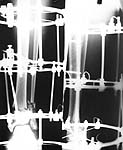

To give the follow up on this patient: A repeat X-ray showed the talus subluxating laterally. A dynamic inversion and eversion strain view pictures showed the lower tibio-fibular syndesmosis opening out. The frame was re-adjusted. Fracture site compressed and valgus corrected. A syndesmotic compression was achieved by adding a washer to the olive and pulling the comminuted lateral malleolus medially. another olive with washer given through talus lateromedially. The equinus that you may see has been corrected. Pictures attached. would welcome critical comments.

Dr.T.I. George, Consultant Orthopaedic Surgeon,

Polytrauma, Microvascular Surgery And Hand Surgery Unit,

Metropolitan Hospital, Trichur, S.India.